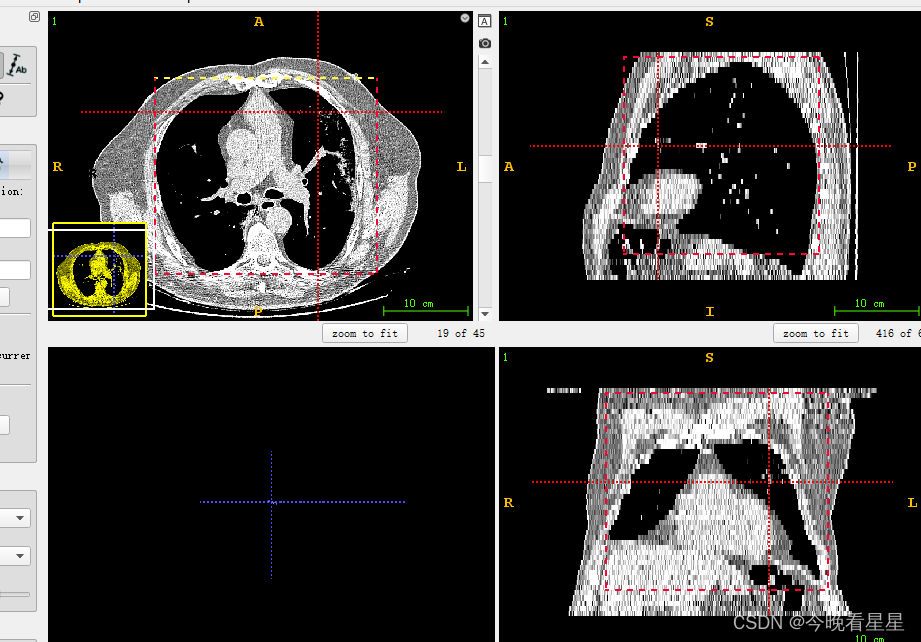

1.1 ITK-Snap视图介绍

在刚开始使用软件的时候,可能上来就被该软件的视图搞蒙了,类似于咱们数学上的三视图,但是他是从CT扫描的视角观察的

三个切片窗口分别为:

- 轴向面(Axial)

- 矢状面(Sagittal)

- 冠状面(Coronal)

常用的有轴向面与冠状面,可以帮助我们进行空间上的定位与标注

4 半自动分割的步骤

使用矩形框进行框选,并在多个视图中确定区域

-

在左侧进行3D分割

- 看第二个视图, 蓝色为丢弃区域,白色为选择的区域,进行CT阈值的调节,来选择想要的部分。参数调整完毕后,选择next进行下一步操作

- 在要扩散的区域选择点,进行自动扩散

- 观察到区域在不断的扩散

- 3D的结果